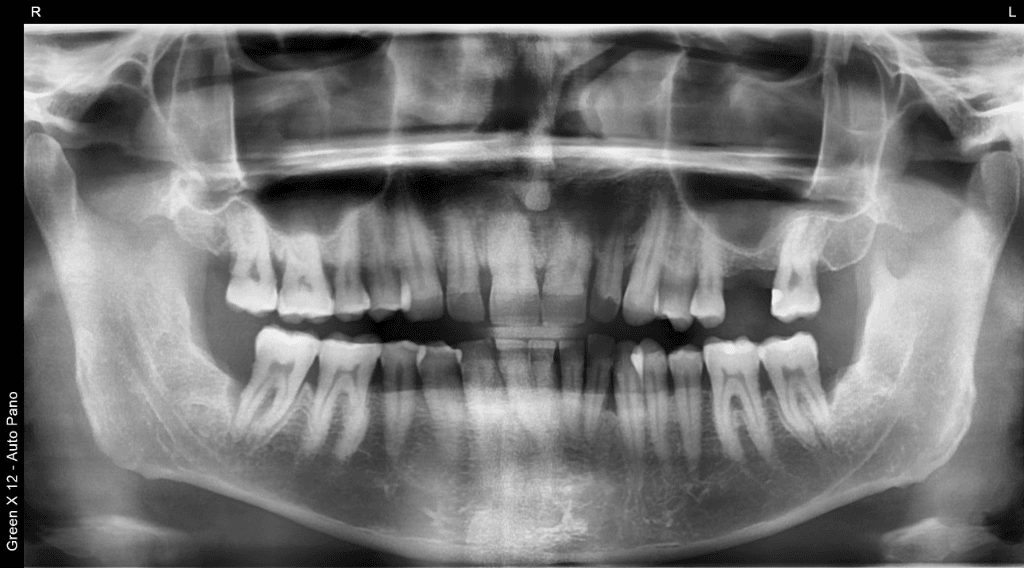

Essential 2D radiographs including panoramic and cephalometric dental x-rays, used for orthodontics, wisdom teeth, and general assessment.

Wide-view X-ray for a general overview.

| Panoramic Dental X-Ray (2D) | Wide-view radiograph for general assessment (wisdom teeth, screening). | $150 |